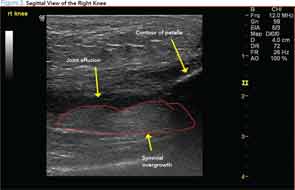

I suggest that, in patient-oriented medicine, patients’ perceptions of MSUS results may promote its expanded use. The images are confusing at first, but with minimal on-the-spot education, the scans can help patients visualize and understand key clinical concepts of their disease process, such as abnormal joint effusion or enlargement (see Figure 2).

My own experience with ultrasound has allowed me to detect synovial fluid with certainty, better direct the injection needle, accurately diagnose shoulder pathology on the spot and immediately share what I saw with the patient.